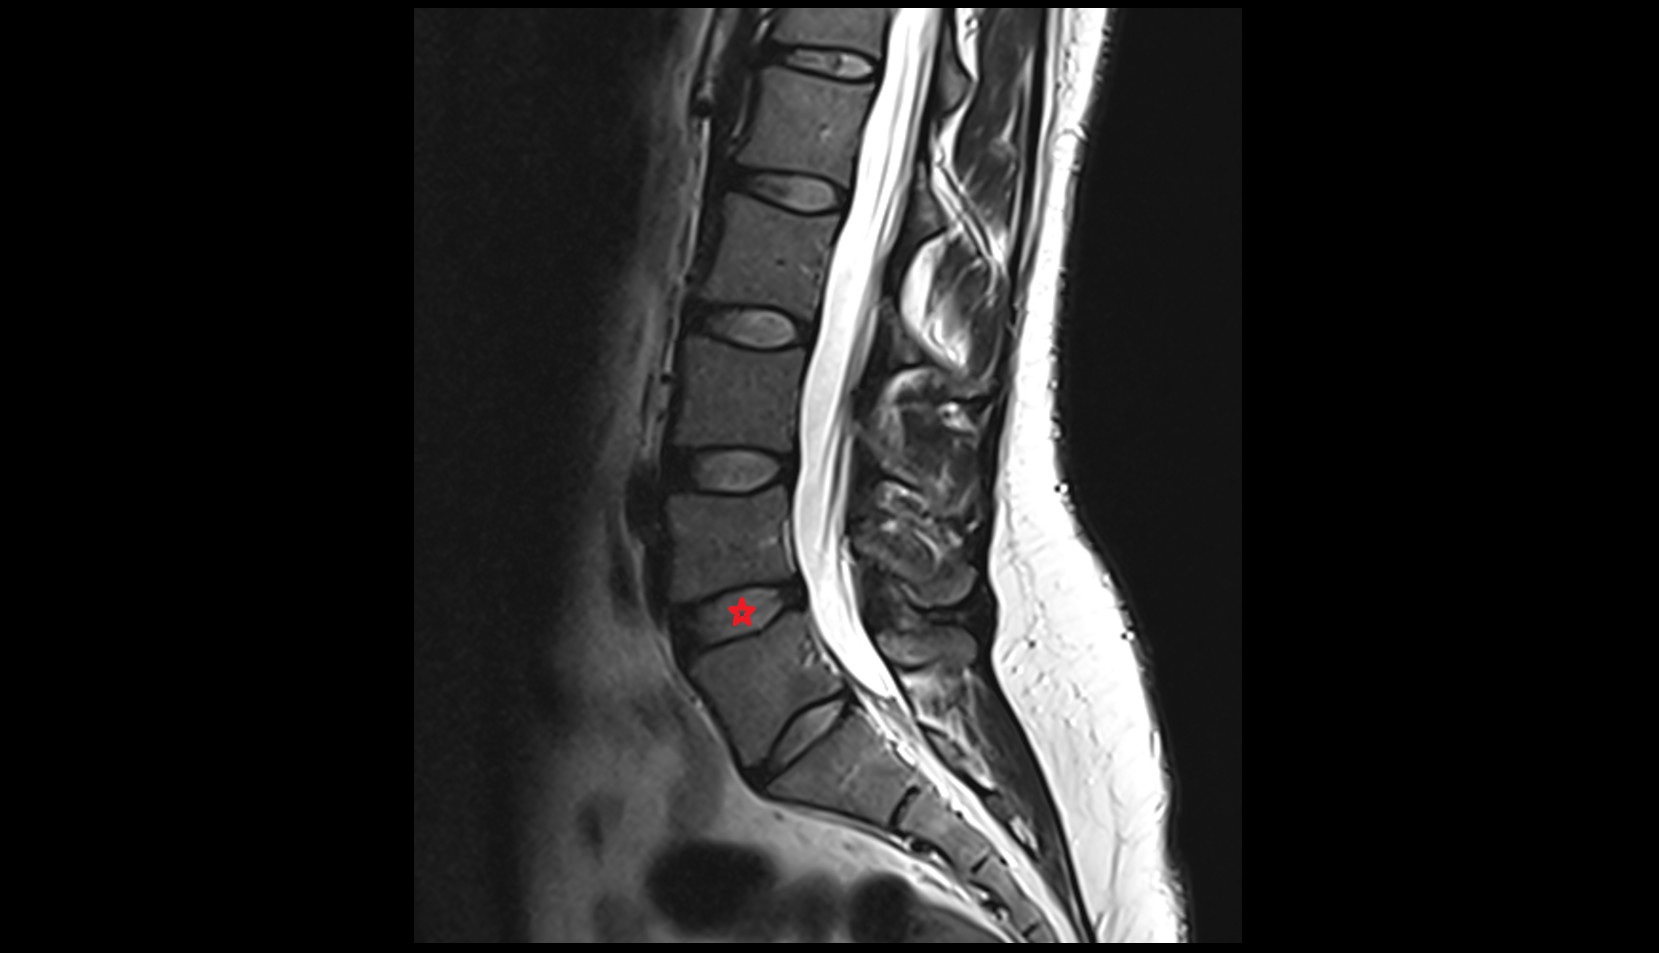

- Conus medullaris

- Cauda equina

- L5–S1 Intervertebral disc

- L4–L5 Intervertebral Disc

- L3–L4 Intervertebral Disc

- Traversing nerve root of spinal nerve

- Exiting nerve root of spinal nerve

- Spinal dura mater

- Spinal epidural space